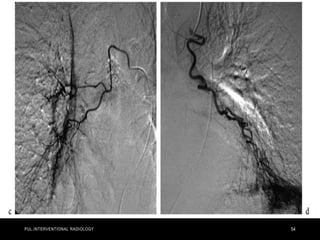

• Pulmonary angiography in a 57-year-old woman in shock from

acute bilateral massive PE. Initial right (a) and left

(b) pulmonary angiograms show near-complete obstruction.

Pulmonary artery pressure was 73/18 mm Hg. Final right (c) and

left

(d) images after suction thrombectomy and catheter-directed

thrombolytic agent injection into each main descending

pulmonary

artery. Pulmonary artery pressure was reduced to 36/16 mm Hg.

(Images courtesy of Daniel Y. Sze.)